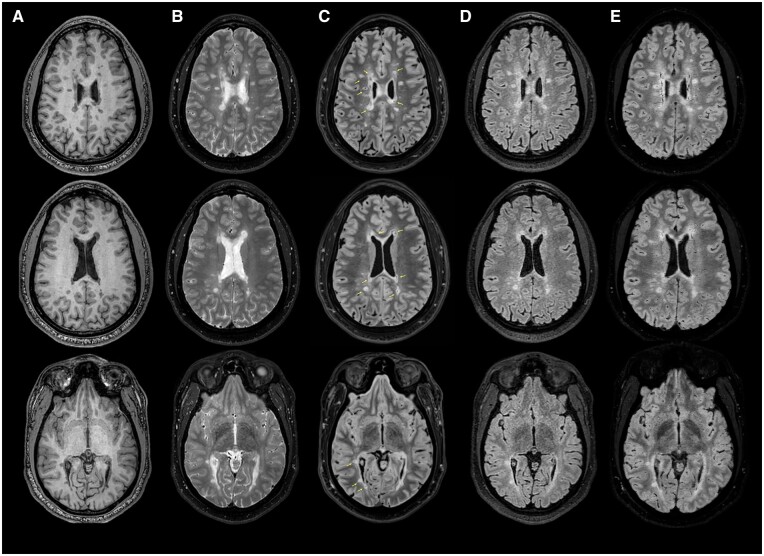

The radiologically isolated syndrome is defined by the presence of incidentally identified T2-weighted hyperintense lesions, highly suggestive of central nervous system demyelination, following an MRI study that is performed for reasons other than for the investigation of symptoms related to multiple sclerosis (MS). These individuals also have no evidence of prior neurological symptoms associated with inflammatory demyelination and no alternative explanation for the observed MRI findings. Recently, the introduction of novel imaging techniques such as the "central vein sign" has improved lesion specificity for MS. In addition, the observation of T2-fluid attenuated inversion recovery (FLAIR) mismatch characteristics associated with gliomas and in those with MS with a higher disease burden appear to provide morphological data that relate to disease severity. The value of T2-FLAIR mismatch characteristics in discrete multi-focal lesions has not yet been well defined. Here, we present the value of a fat-suppressed T2-FLAIR sequence in the identification and characterization of T2-weighted hyperintensities resulting from inflammatory demyelination.